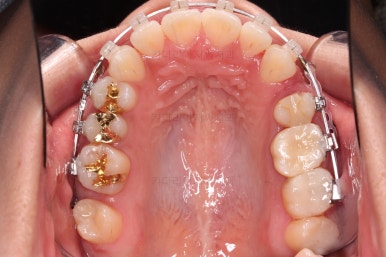

마찬가지로 초진 시 입안의 모습입니다.

입안 사진을 보니 문제점이 보이죠.

바로 어금니가 없는 상태였습니다.

장치를 부착해서 가지런하게 하고요.

발치가 필요한 치아를 하나씩 뽑아나갑니다.

어금니 발치 공간이 어마어마하게 넓죠?

이번 부산사랑니교정 환자분이 선택하신 장치는 데이몬 클리어라고 하는 자가결찰 세라믹 장치인데요.

현존하는 세라믹 장치 중에 가장 심미적인 장치입니다.

철사를 잡아주는 뚜껑은 금속으로 되어있는 클리피씨나 엠파워 클리어에 비해 뚜껑까지도 세라믹으로 되어있기 때문이죠.

윗니도 발치를 했고요.

발치공간을 서서히 줄여 나갑니다.

이제 미니스크류가 등장합니다.

상하좌우 발치 공간의 크기와 위치가 제각각이라서 당겨지는 양과 속도가 차이납니다.

그래서 미니스크류를 반드시 써줘야 합니다.